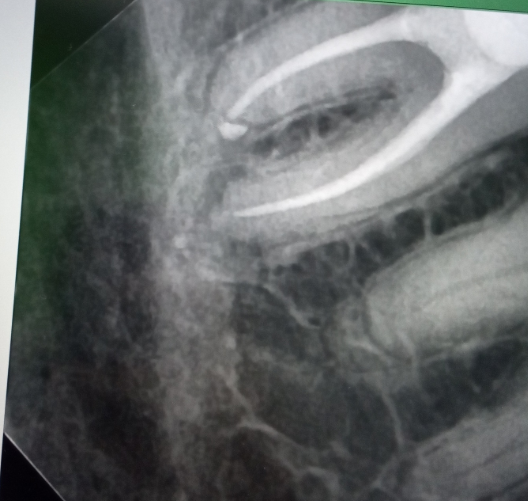

alewka213213 Опубликовано 10 декабря, 2024 Автор Поделиться Опубликовано 10 декабря, 2024 (изменено) В 08.12.2024 в 19:48, Carioznik сказал: Дело в инфекции, которая находится внутри зуба, а за пределами зуба -это её следствие. Нет зуба - нет инфекции. Это вариант удаления, он даёт 100% результат. Почистить каналы -тоже равно убрать инфекцию. Это вариант лечения, но даёт уже не 100 % результат. Хочется сохранить зуб (показаний к удалению, кстати, пока не видно) - перелечивайте. Не хотите лечить - удаляйте. Решать Вам. Cходил, чтобы перелечить, но решили не делать этого, так как врач заметил, что кажется воспаление уменьшается! И это при том что зуб без нерва, мы ничего не делали, а оно вон как... Или нам кажется? По крайне мере увеличения вроде нет. Вот, тоже выскажите мнение, пожалуйста. Пол года назад: Сейчас: Изменено 10 декабря, 2024 пользователем alewka213213 Ссылка на комментарий

Carioznik Опубликовано 10 декабря, 2024 Поделиться Опубликовано 10 декабря, 2024 (изменено) 57 минут назад, alewka213213 сказал: кажется воспаление уменьшается! Оченивать динамику нужно по КТ. По обычным снимкам всё может быть очень обманчиво. В зависимости от проекции (а её невозможно, при обычном снимке, сделать одинаковую)- будет разный размер. Вот вам пример: посмотрите на свою ладонь, а потом поверните ее ребром (сначала она была по площади - большая, а когда повернули - стала вдруг уже маленькая) Изменено 10 декабря, 2024 пользователем Carioznik 1 Ссылка на комментарий